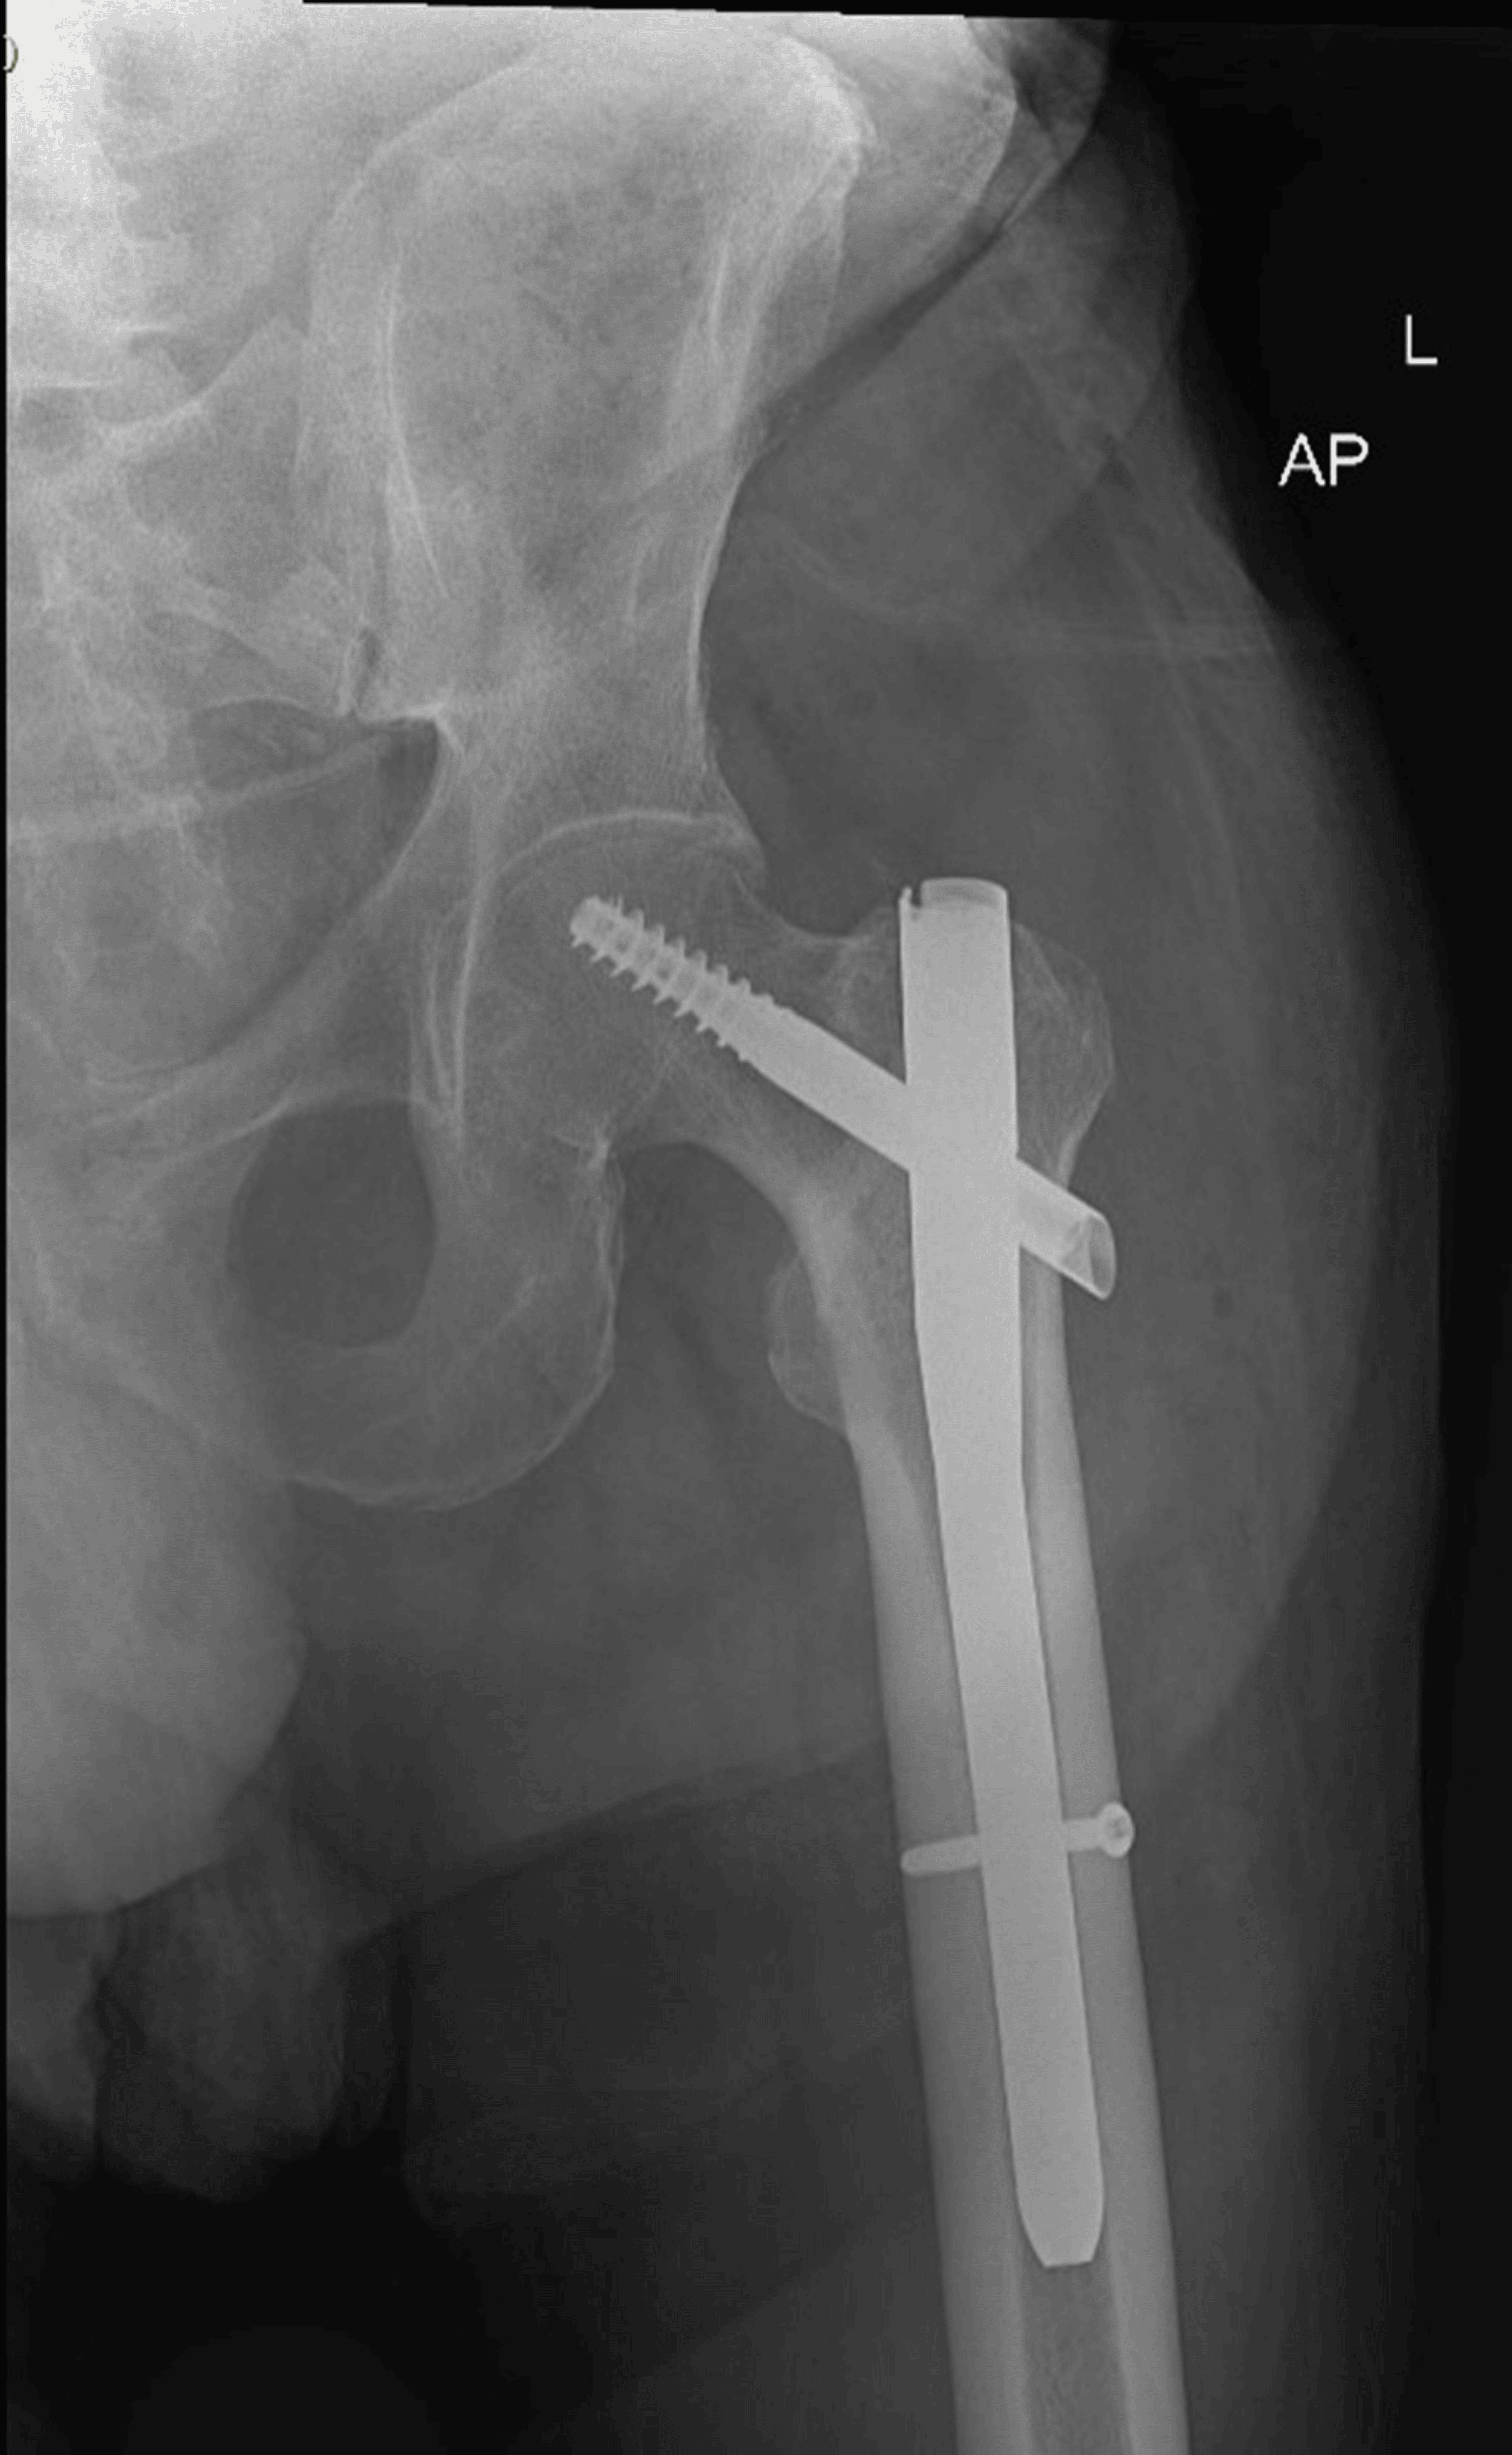

An 80-year-old male presented to the Emergency Department following a fall resulting in a closed left femoral neck fracture. He was scheduled for closed reduction and internal fixation with a trochanteric femoral nail advanced (TFNA) as confirmed by X-ray pelvis showing a “mildly displaced intertrochanteric fracture of left femur” (Figure 1). His medical history included coronary artery disease with prior coronary stenting (echocardiography revealed preserved systolic function (ejection fraction 55-60%), Grade I diastolic dysfunction, and no valvular lesions, regional wall motion abnormalities, or pulmonary hypertension, indicating low perioperative risk for anesthesia), poorly controlled hypertension, end-stage renal disease requiring twice-weekly hemodialysis, and well-controlled type 2 diabetes mellitus. Additional conditions included benign prostatic hyperplasia, bilateral renal cortical cysts, and cystitis. His medications comprised bisoprolol, aspirin, enoxaparin (substituted for clopidogrel preoperatively), insulin, ezetimibe, and topical beta-sitosterol, with no reported drug allergies.

The surgical procedure, involving closed reduction under fluoroscopy and TFNA fixation, lasted 95 minutes (Figure 7). Sedation was maintained through the procedure with a second dose of 6 mcg of dexmedetomidine. Hemodynamic stability was maintained with minimal intravenous phenylephrine (5-20 mL/hour at 100 mcg/mL). Intraoperative fluids comprised 500 mL sodium chloride and 200 mL 5% albumin in normal saline, with 1.5 g cefuroxime administered for prophylaxis. Vascular access was secured via a 20-G peripheral intravenous line (left basilic vein) and a right radial arterial line, removed post-procedure. Estimated blood loss was minimal (100 mL), and no blood transfusions were required. The procedure concluded without intraoperative complications.